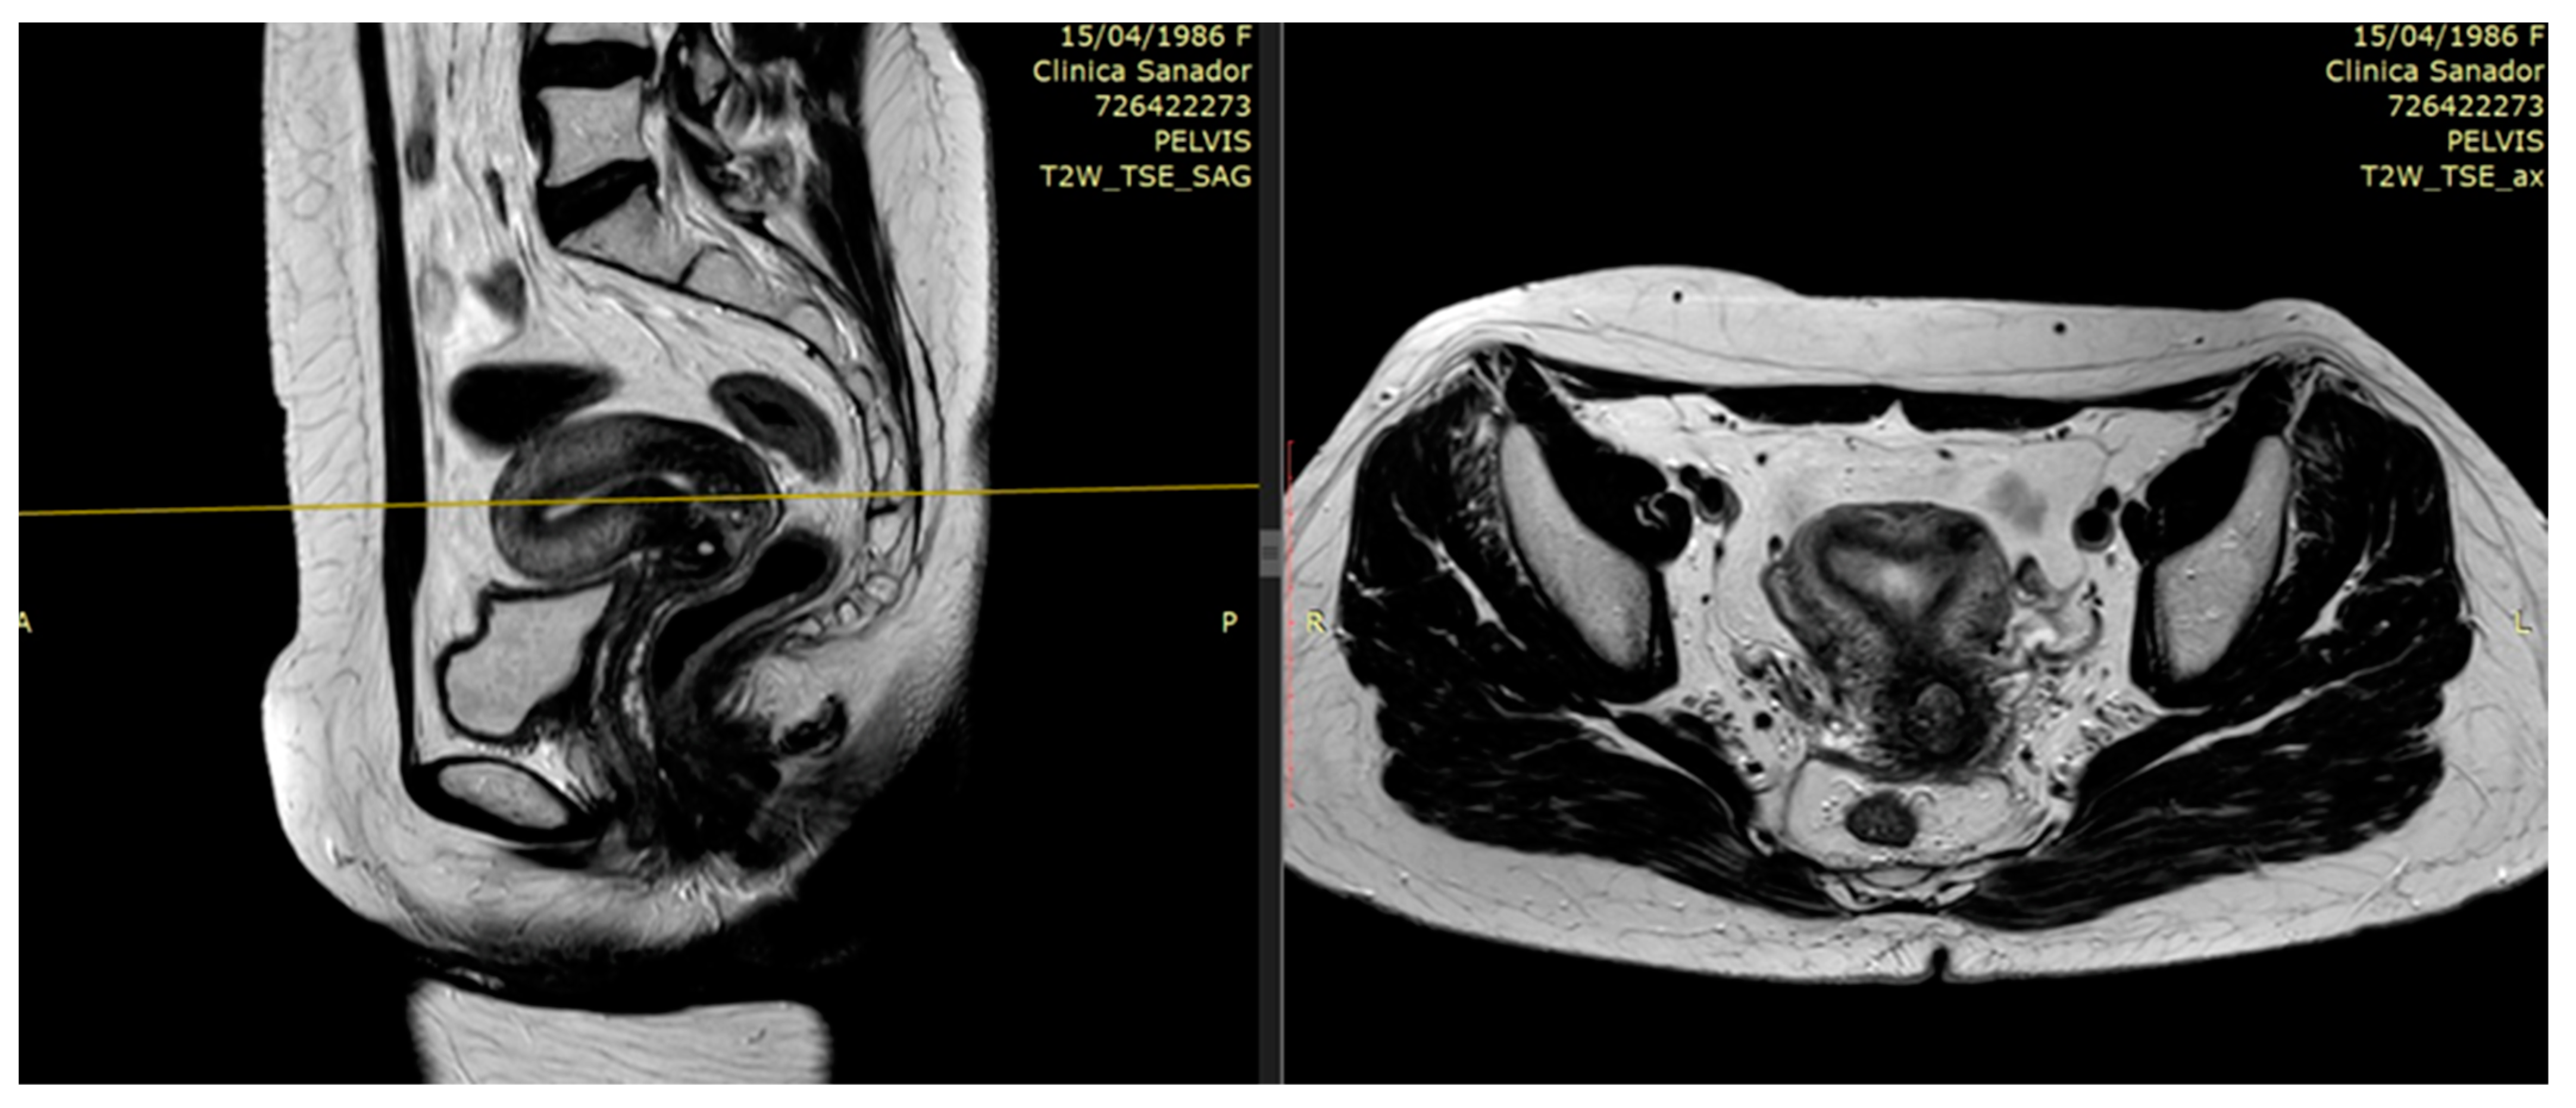

2.1. The Role of MRI